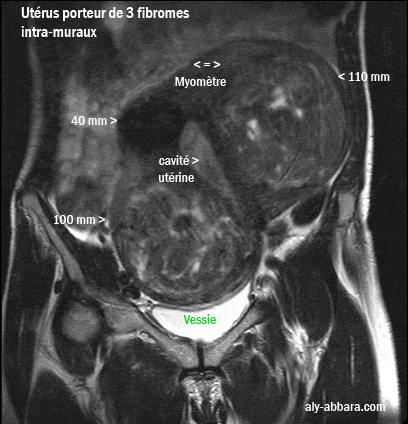

Coupe frontale de l'utérus et des deux tiers inférieurs de la cavité abdominale

Utérus polymyomateux

porteur de 3 myomes intra-muraux de 110, 100 et 40 mm de grand axe

La différence de l'aspect entre les trois fibromes est due au fait que les deux volumineux myomes

(110 et 100 mm) présentent de multiple phénomènes de remaniement nécrotique.

Cette différence est visible avant et après l'injection de produit de contraste = gadolinium.